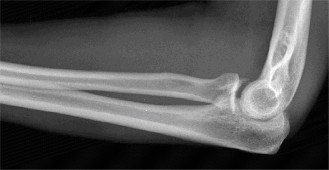

The correct answer is (A). The first step in management of this patient is obtaining a complete set of x-rays to rule out a missed shoulder dislocation (as seen in Fig. 2–45). Answers C to E describe various treatment modalities, but these cannot be instituted without a firm diagnosis. An MRA (Answer B) is most commonly used when a labral tear is suspected, but an x-ray would be the first imaging modality utilized.

Figure 2–45 Axillary view demonstrating a chronic anterior shoulder dislocation.

Chronic shoulder dislocations are relatively uncommon injuries but represent a significant challenge even for the experienced provider. There are varying opinions on what duration of time a shoulder needs to be dislocated to be termed “chronic.” Three to four weeks is a commonly accepted timeframe, although any dislocation that is not identified and treated at the time of injury can be defined as chronic. This

most frequently occurs in a polytrauma patient where other, more life-threatening injuries, may cause a provider to overlook the shoulder. Treating chronic, glenohumeral dislocations can be very challenging, so the most important goal is preventing the problem by minimizing the risk of missing an acute dislocation. This is most easily done with a complete set of x-rays on any patient with a suspected shoulder injury. Obtaining an axillary view or Vallpeau view is essential as these views will most clearly demonstrate the position of the humeral head with respect to the glenoid. An AP and even a scapular Y view are insufficient to diagnose a shoulder dislocation, and an inability to obtain a Grashey view should clue the provider into a possible dislocation.